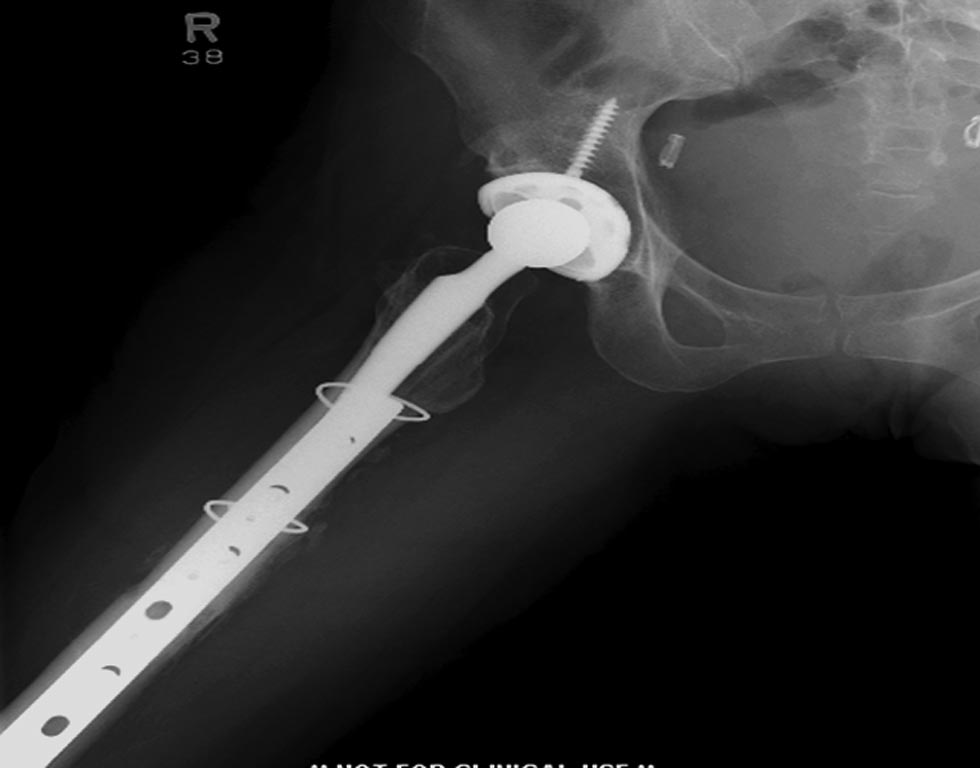

На 25 день с момента травмы операция на Jackson table с боковым обширным

доступом. Удаление стержней с местной обработкой. В тазобедренном

суставе удаление головки, на дне вертлужной впадины полная отслойка

хряща. Вертлужный компонент с одним винтом и короткая ножка -  Fitmore

Выписана. Нагрузку разрешили на левой стороне, а полная в 3 мес.  Здесь

снимки при амбулаторном наблюдении​: послеоперационно, 2 мес, 3 мес и 6

мес. Нагрузка полная, отсутствует хромота, и нет жалоб.